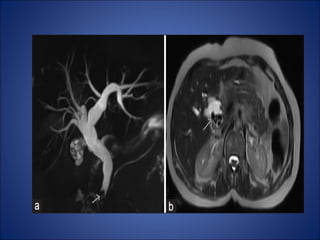

Pancreatic divisum

• The ventral bud failed to fuse

• The pancreatic head and

uncinate process are drained

through the major papilla.

• The body and tail of the

pancreas are drained through

the minor papilla.

• As a result ,the dorsal

pancreatic duct drains most of

the pancreas via the minor

papilla that may lead to

recurrent attack of pancreatitis

Annular Pancreas